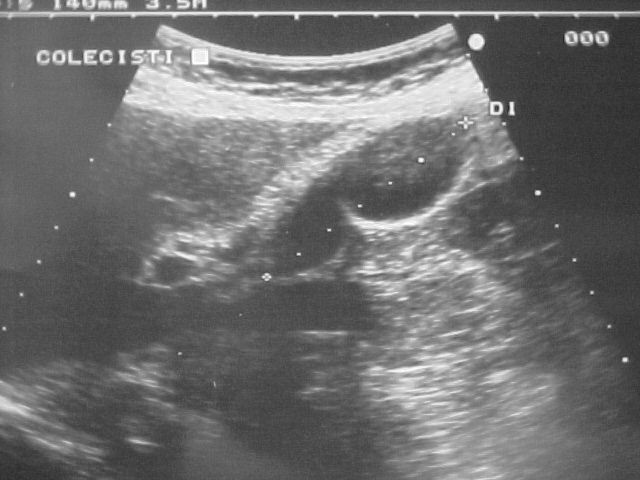

Gastroeneterologo Milano